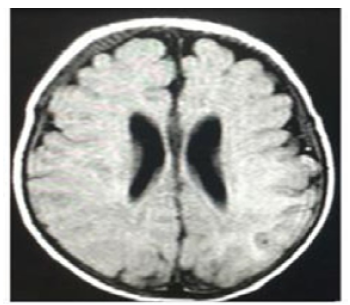

At 27 days of life, the patient had a seizure with recurrent focal episodes that later became generalized and resulted in post-seizure paralysis in the right upper limb, requiring the administration of midazolam (single dose of 0.2 mg/kg) and the initiation of maintenance doses of phenobarbital (10 mg/kg/day) and valproic acid (30 mg/kg/day), medications that led to the resolution of the seizure. Once he was stable, on the 28th day of life, a lumbar puncture was performed, which allowed to rule out neuroinfection. Then, at 30 days of life, a contrast-enhanced magnetic resonance imaging (MRI) scan of the brain was performed, and no abnormal findings were observed (Figure 3).

Contrast-enhanced magnetic resonance imaging of the brain (gadolinium); cross-sectional view.

Figure 3: Contrast-enhanced magnetic resonance imaging of the brain (gadolinium); cross-sectional view.

Source: Document obtained during the study.

On the other hand, it has been reported that seizures occur when glucose levels in the central nervous system drop below the normal level (80-90 mg/dL) to less than 20-30 mg/dL, a situation which, if prolonged, causes neuronal death attributable to hypoglycemia.14 However, although there is not much information on the subject, the pathophysiological mechanism of brain damage associated with HI/HA syndrome is complex and multifactorial and does not seem to be the result of a lesion directly caused by hypoglycemia.3,4,15 Possible explanations for seizure activity include persistent hypoglycemia or chronic hyperammonemia, as well as decreased levels of glutamine and the neurotransmitter GABA due to increased activity of the enzyme glutamate dehydrogenase in the brain.3,16 In this regard, it has been reported that when hypoglycemia occurs, the main excitatory amino acid glutamate is poorly reabsorbed due to its extreme secretion in the synaptic area and insufficient energy-dependent channels, resulting in increased amounts of secondary extracellular glutamate, which, in turn, induces seizures.17 In the case reported here, the absence of structural lesions on brain MRI supports this statement.